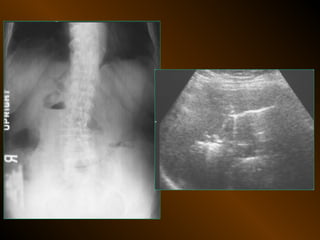

TỤ DỊCH TRONG PHÚC MẠC

• X QUANG QUY ƯỚC

– Trong tiểu khung

– Dọc hai bên hông

– Giữa bụng

• SIÊU ÂM

– Phản âm trống, chuyển dịch

– Lượng ít

– Bản chất dịch

• X QUANG CẮT LỚP ĐIỆN TOÁN

– Mật độ

– Vị trí

– Nguyên nhân